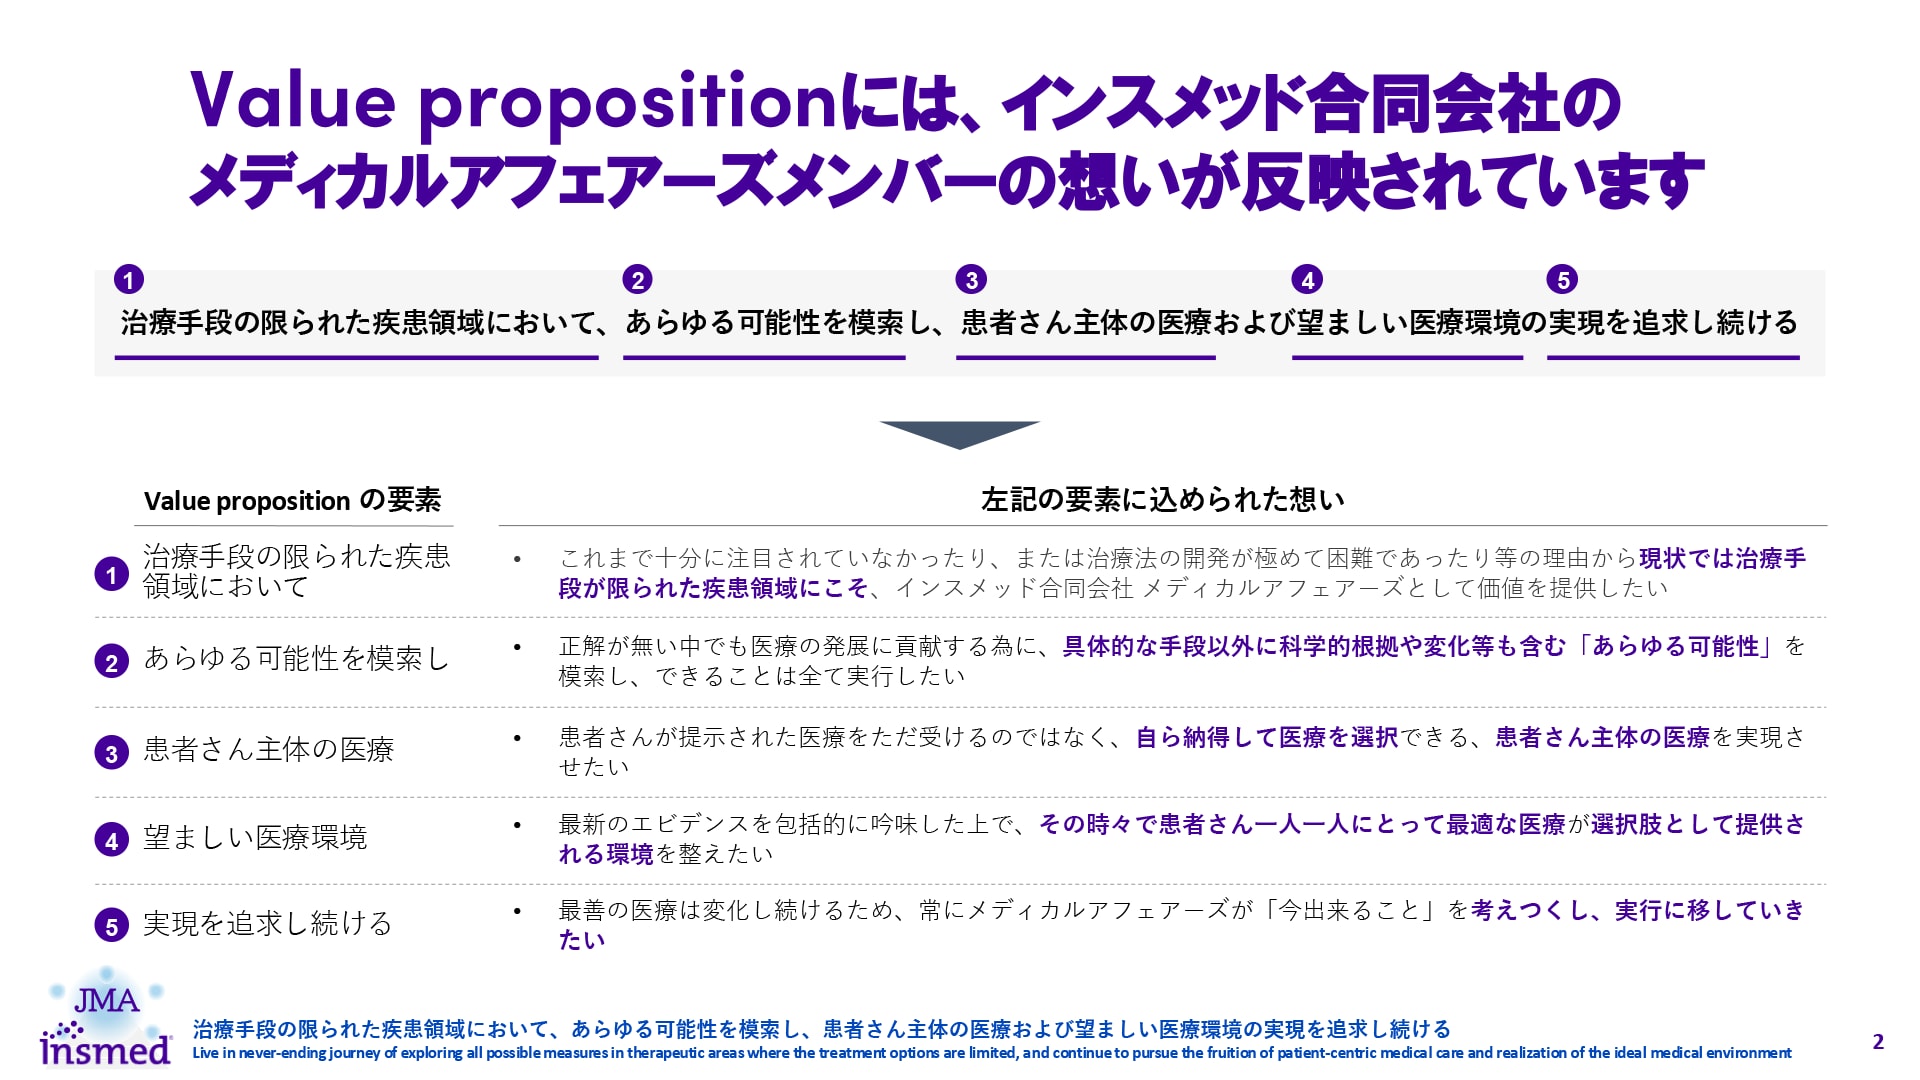

気管支拡張症は、不可逆的に進行する慢性炎症性疾患であり、近年世界的に有病率の増加が示唆され注目が集まっています。

本サイトは気管支拡張症を詳細に解説することで、医療従事者の方々のこの疾患の認知・理解を高め、適切な医療・ケアに活かしていただく目的で開設いたしました。